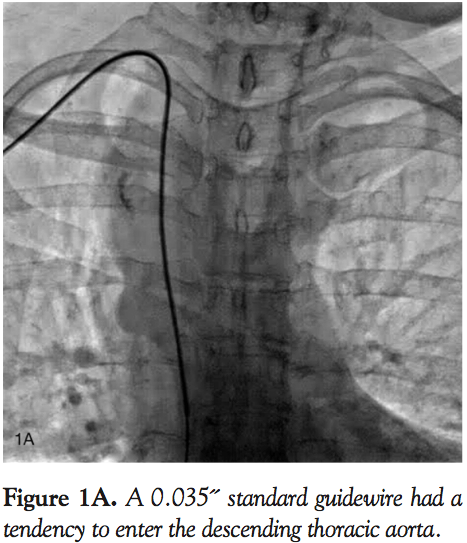

In this patient, the catheter had a tendency to dive repeatedly into the descending thoracic aorta, maintaining right paraspinal position (Figure 1A). It was initially misinterpreted as entry into the right atrium through the superior vena cava. However, pressure tracing was suggestive of arterial pressure. Angiogram with pigtail catheter was done to define anatomy, and confirmed the right paraspinal position of the descending thoracic aorta (Figure 1B). Another angiogram in aortic arch position confirmed innominate artery origin at an acute